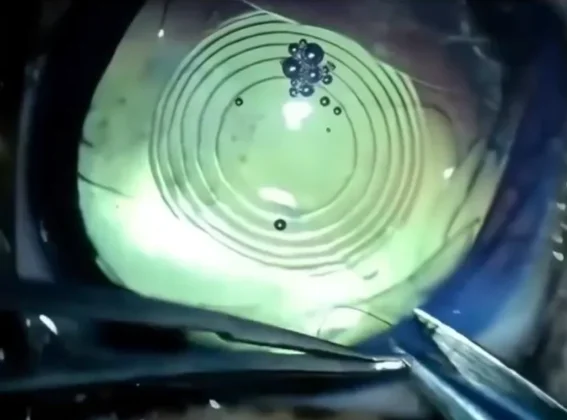

Em seguida, o vídeo mostra o procedimento cirúrgico. Em casos de cachorros idosos, os veterinários removem o cristalino opaco e o substituem por uma lente artificial. O tratamento é realizado por especialistas e costuma trazer melhora significativa na qualidade de vida do animal.

Após o procedimento, o médico realiza um teste simples para avaliar o resultado e aproxima uma das mãos dos olhos do cachorro, que reage piscando. O movimento confirma que a visão foi restaurada.